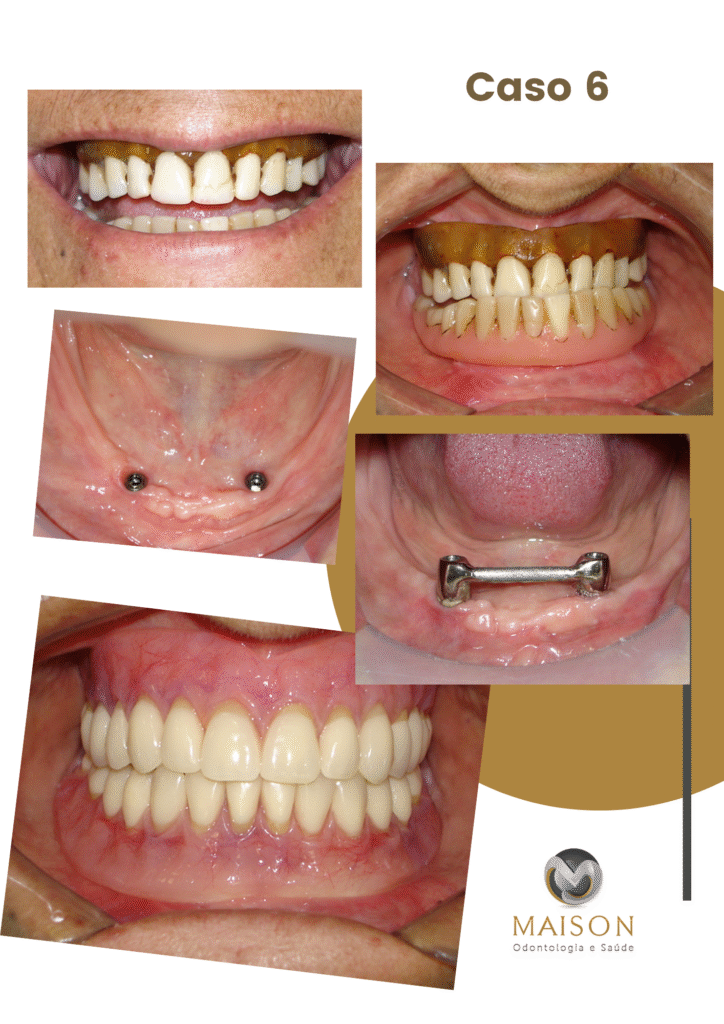

Transformação do Sorriso

- Técnicas Avançadas de Reabilitação Oral: Implantes Unitários, Múltiplos, Overdenture, Protocolo, Técnica Facco no osso Zigomático; realizamos todos o tipos de próteses sobre implante.